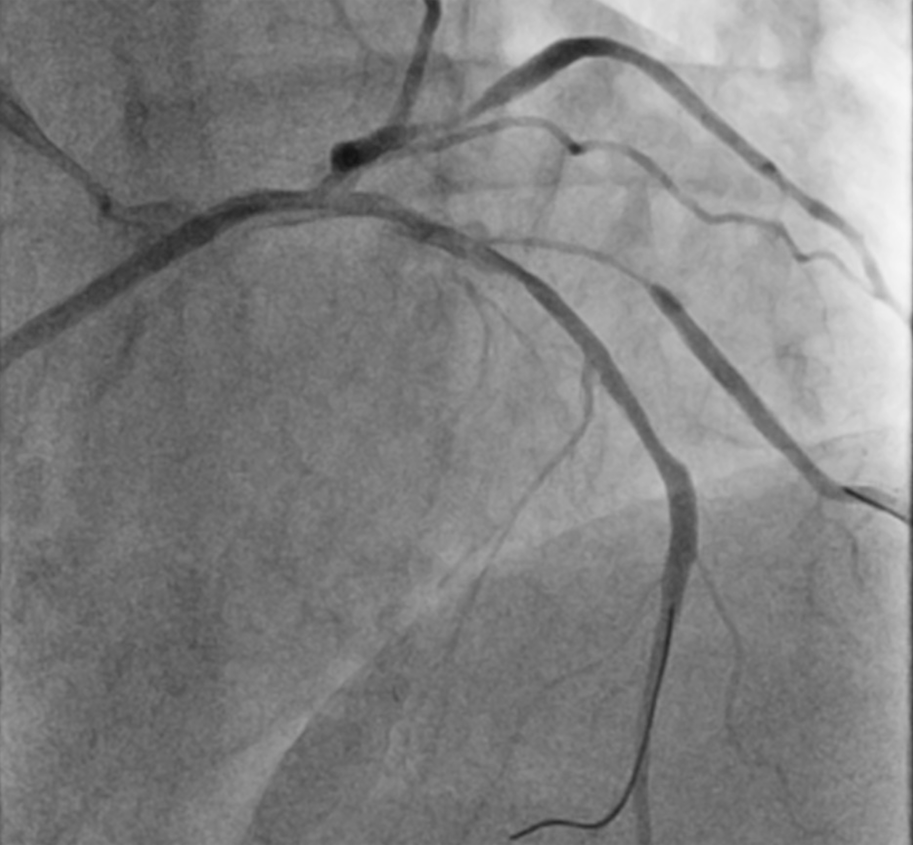

A 75-year-old man was admitted for non-ST-segment elevation myocardial infarction (NSTEMI). Coronary angiography showed focal severe disease at obtuse marginal artery (OM) and severe medina 1,1,1 bifurcation disease involving proximal to middle left anterior descending artery (LAD) and a sizable diagonal branch (Figure 1A, Video 1). With a 6-French extra backup (EBU) 3.5 guide catheter, the LAD was wired with a workhorse guidewire. The diagonal branch had a retroflex takeoff and initial wiring was subintimal (Figure 1B). Parallel wire technique (PWT) with Gaia Next 1 (Asahi Intecc) successfully rewired the true lumen and steered into the distal part of the diagonal branch (Figure 1C, D; Video 2). The LAD was provisionally stented with the diagonal branch protected by jailed balloon technique (JBT) of a 2.0 mm semi-compliant balloon, followed by stenting of the OM (Figure 1E). The final angiographic results were good (Figure 1F, Video 3).